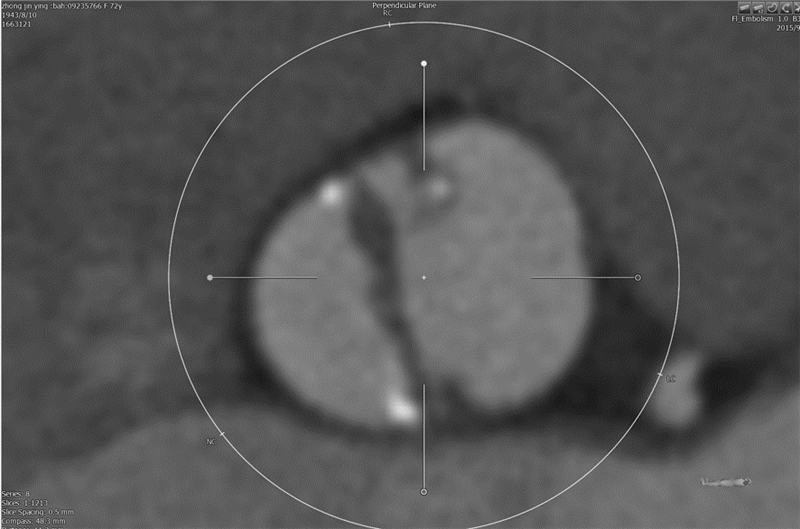

1 资料与方法 1.1 一般资料病例1:患者女,72岁,因“反复胸闷乏力10余年,加重3个月余”入院,有血吸虫肝病、血小板减少症、肾功能不全病史。入院查体发现主动脉瓣听诊区可闻及4 /6级收缩期喷射样杂音。超声心动图:主动脉瓣钙化性病变重度狭窄,平均跨瓣压差(PGmean)61 mmHg(1 mmHg=0.133 kPa),最大跨瓣流速(Vmax)5.08 m/s,瓣口面积(AVA)0.70 cm2,主动脉瓣轻度关闭不全,舒张末期左心室直径(LVEDD)4.51 cm,左室射血分数(LVEF)64.5%。CTA提示:二叶式主动脉瓣(type 0)(图 1),中等程度钙化;瓣环内径:直径22.2 mm×22.5 mm,平均23.1 mm,由面积424.4mm2计算的直径23.2 mm,由周长74.2 mm计算的直径23.6 mm。诊断:①心脏瓣膜病主动脉瓣重度狭窄伴轻度关闭不全心功能Ⅲ级;②血吸虫肝病;③血小板减少症 ;④慢性肾脏病4期。美国胸外科医师学会(STS)评分4.58%,但因合并多器官疾病,心脏瓣膜团队建议TAVR手术。

|

| 图 1 二叶式主动脉瓣畸形(Type0) Fig 1 Bicuspid aortic valve (Type 0) |